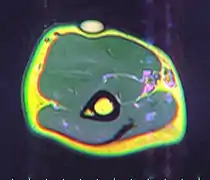

A physical exam is typically the easiest way to diagnose it. Rarely, a tissue biopsy or imaging may be required. The imaging modality of choice is magnetic resonance imaging (MRI) because it has superior sensitivity of distinguishing it from liposarcoma as well as mapping the surrounding anatomy.[22]

Usually, treatment of lipomas is not necessary, unless they become painful or restrict movement. They are usually removed for cosmetic reasons if they grow very large or for histopathology to verify that they are not a more dangerous type of tumor such as a liposarcoma.[13] This last point can be important, as the characteristics of a tumor are not known until after it is removed and medically examined.

Lipomas are normally removed by simple excision.[27] The removal can often be done under local anesthetic and takes less than 30 minutes. This cures the great majority of cases, with about 1–2% of lipomas recurring after excision.[28] Liposuction is another option if the lipoma is soft and has a small connective tissue component. Liposuction typically results in less scarring; however, with large lipomas, it may fail to remove the entire tumor, which can lead to regrowth.[29]